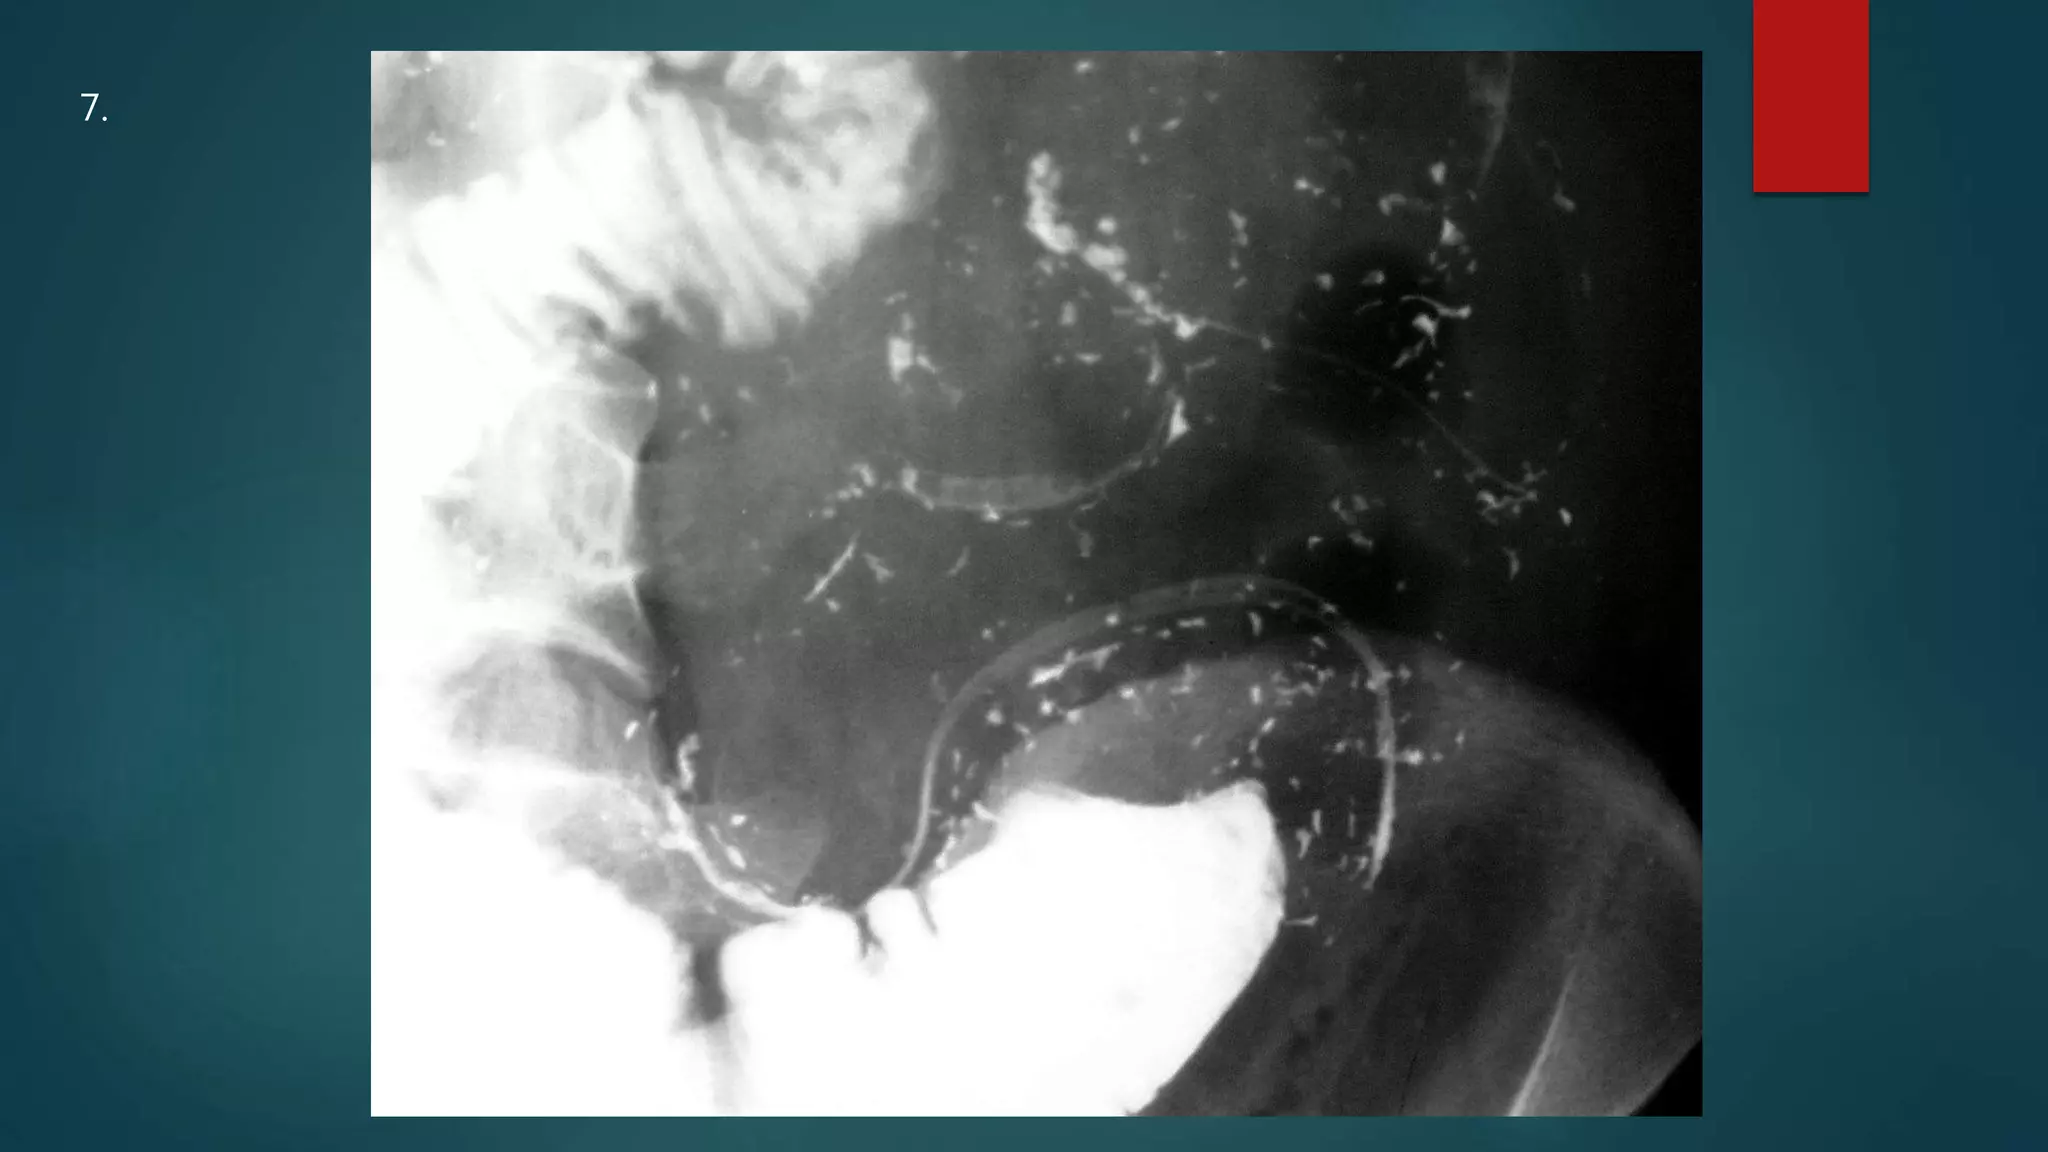

This document appears to be a medical report discussing several patients. It mentions a 35-year-old who was in a severe motor vehicle accident and an 81-year-old with a history of a non-vegetarian diet who had a perforated bowel from a chicken bone. The document provides few other details across its 25 numbered entries and was authored by Dr. Anish Choudhary for junior year 3 on May 30, 2016.